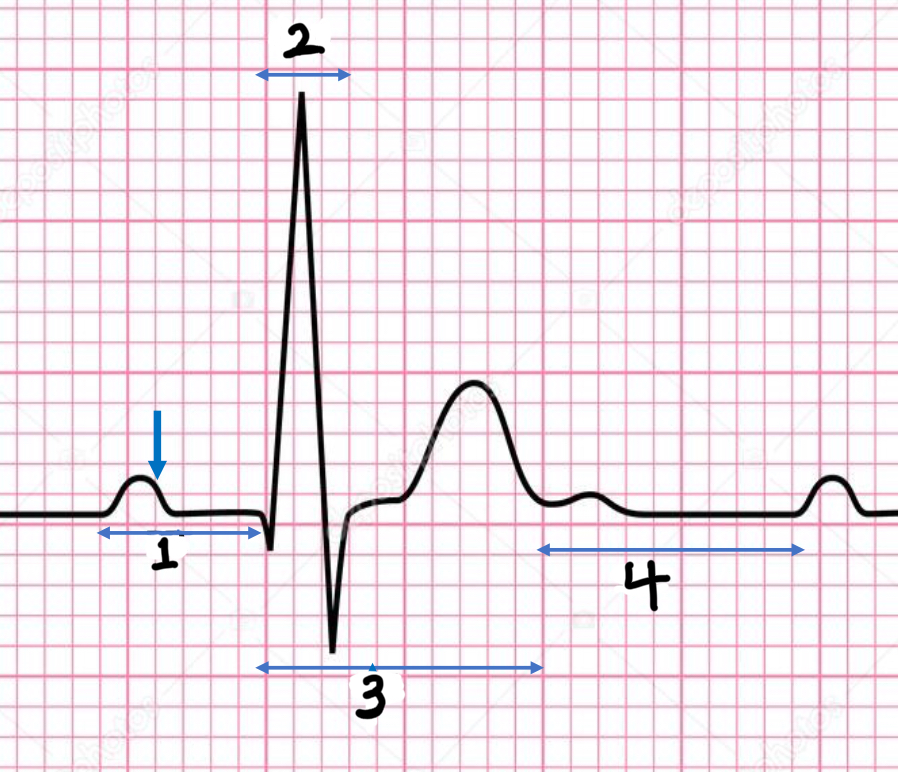

P wave

atrial depolarization

Precedes atrial contraction

QRS complex

ventricular depolarization

Precedes ventricular contraction

T wave

ventricular repolarization

PR interval

Name #1

QRS interval

Name #2

QT interval

Name #3

TP interval

Name #4

PR interval

time from beginning of the P wave to the beginning of the QRS complex

QRS interval

Time from beginning of the QRS complex to the end of the QRS complex

QT interval

Time from beginning of QRS complex to the end of the T wave

TP interval

Time from end of T wave to the beginning of P wave